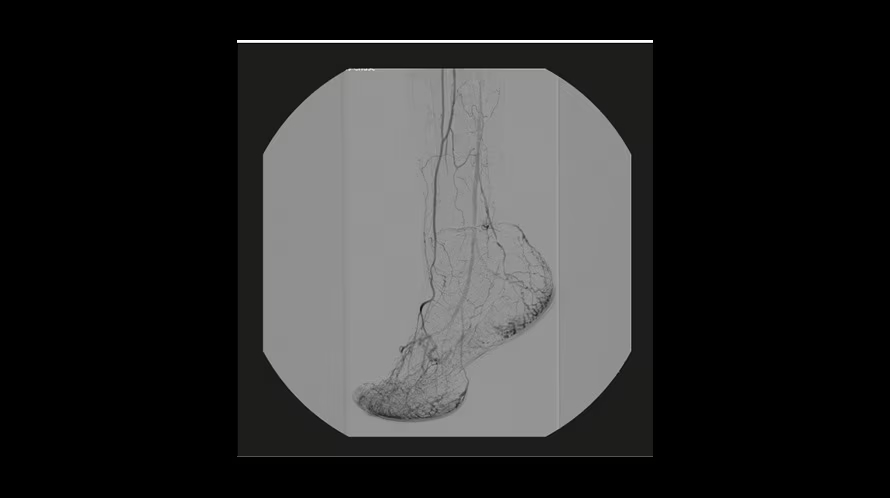

GE OEC Elite CFD относится к мобильным рентгенохирургическим системам премиум-уровня и предназначена для проведения интраоперационных рентгеноскопических и рентгенографических исследований в хирургии, травматологии, ортопедии, сосудистых и эндоваскулярных вмешательствах, нейрохирургии и урологии. Плоскопанельный КМОП-детектор с полем обзора 21×21 см, высоким динамическим диапазоном и частотой до 30 кадров/с обеспечивает детализированную визуализацию костных структур, мягких тканей и контрастированных сосудов в режиме реального времени. Передача изображения 1:1 на 32-дюймовый 4K-монитор просмотровой станции позволяет хирургу уверенно ориентироваться в операционном поле, контролировать положение инструментов и имплантов, минимизируя количество повторных экспозиций.

| Цифровая субтракционная ангиография (DSA) | Вычитание фоновых структур для повышения видимости сосудистого русла при контрастных исследованиях. |

| Сосудистые и навигационные режимы | Специализированные профили (Vascular, Cardiac, Roadmapping) для визуализации сосудов и навигации проводников. |